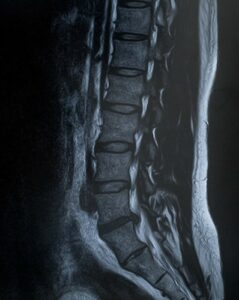

椎間板ヘルニアや脊柱管狭窄症、ぎっくり腰など、あらゆる疾患に付きまとっている坐骨神経痛は、多くの方を悩ませています。

・椎間板ヘルニア

・脊柱管狭窄症

・腰椎すべり症

・腰椎分離症